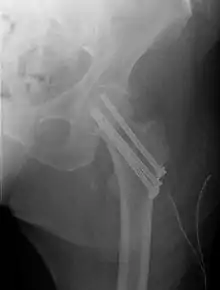

Closed reduction may not be satisfactory and open reduction then becomes necessary.[42] The use of open reduction has been reported as 8-13% among pertrochanteric fractures, and 52% among intertrochanteric fractures.[43] Both intertrochanteric and pertrochanteric fractures may be treated by a dynamic hip screw and plate, or an intramedullary rod.[42]

Subtrochanteric fractures may be treated with an intramedullary nail or a screw-plate construction and may require traction pre-operatively, though this practice is uncommon. It is unclear if any specific type of nail results in different outcomes than any other type of nail.[44]

A lateral incision over the trochanter is made and a cerclage wire is placed around the fracture for reduction. Once reduction has been achieved a guide canal for the nail is made through the proximal cortex and medullary. The nail is inserted through the canal and is fixated proximally and distally with screws. X-rays are obtained to ensure proper reduction and placement of the nail and screws are achieved.[45]